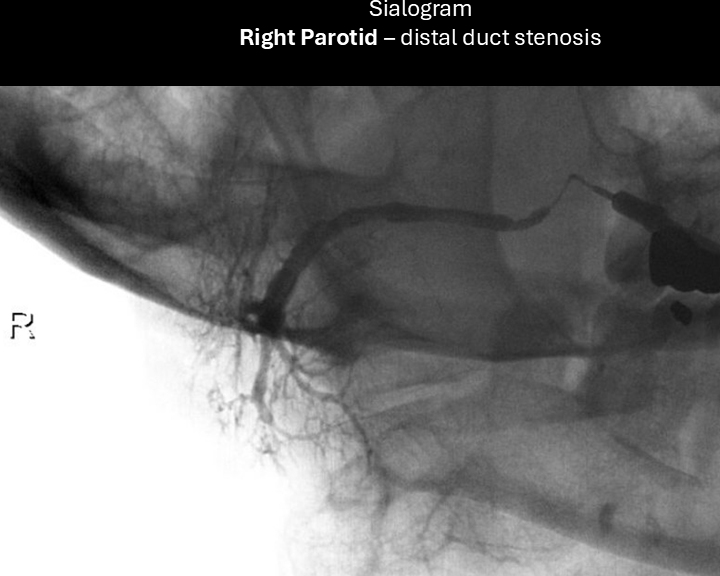

Sialogram:

Performed with 24-gauge angiocatheter - following sialogram, further dilation of duct with 22-gauge angiocatheter over 0.015-inch guidewire - unable to advance 20-gauge catheter.

right sialogram 3

right sialogram 4